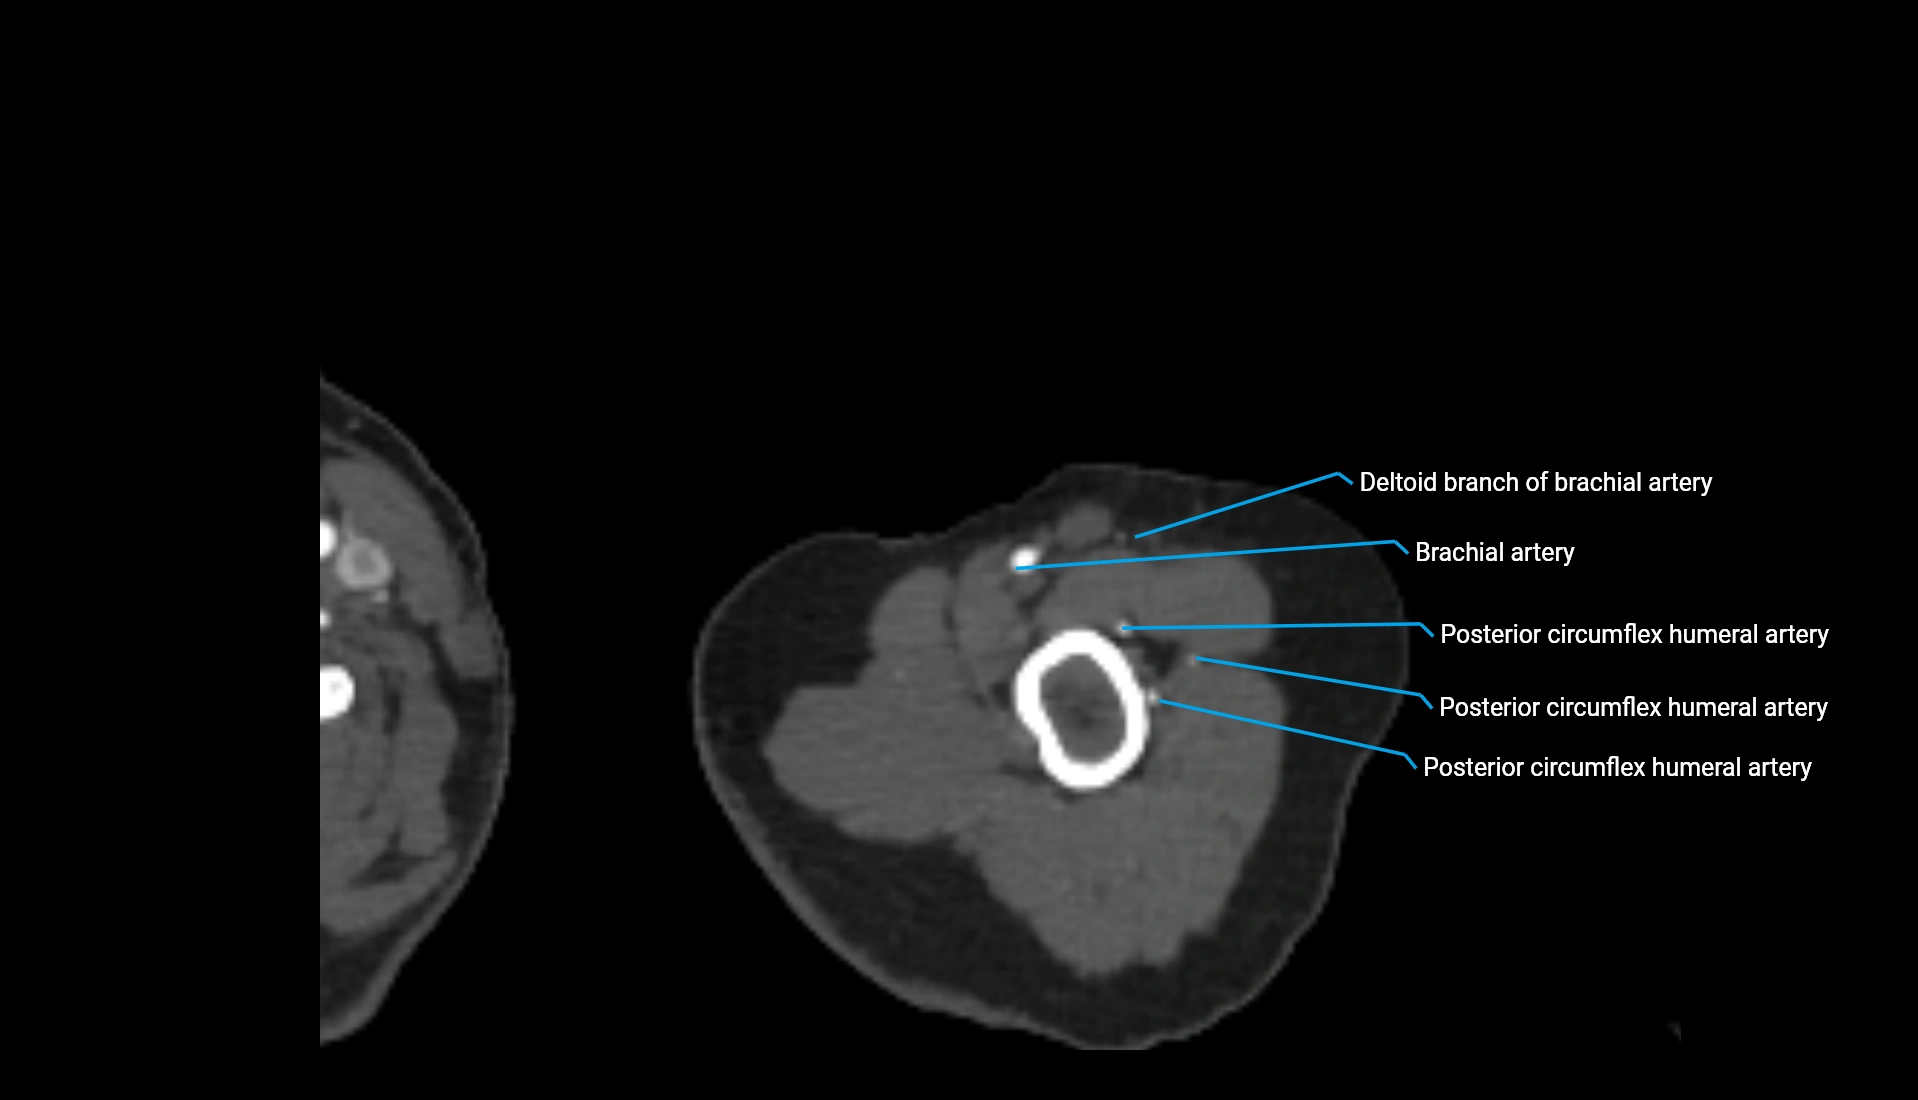

CT Appearance

Non-Contrast CT:

• Cortex: High-density, sharply defined

• Subchondral bone: Dense cancellous matrix

• Articular surface: Smooth concave contour articulating with the capitellum

• Excellent for evaluating bone integrity, alignment, and subtle fractures

Post-Contrast CT:

• Bone: No enhancement

• Joint capsule and synovium: Mild enhancement outlining the joint

• Improves contrast between soft tissues and bony margins

• Useful in detecting subtle joint abnormalities or postoperative changes